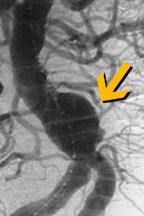

الإجراء يتضمن إستعمال قسطرة لإدخال أداة تسمى وصلة حلقة فاتحة Stent Graft. الحلقة الفاتحة توضع داخل الشريان في موقع التمدد. يجرى الدم خلال الحلقة الفاتحة، مما يؤدي إلى خفض الضغط على جدار الشريان الضعيف. هذا الإنخفاض في الضغط يمكنه أن يمنع التمدد من تفجير الشريان.

حديثا بدأ الأخصائيون بإستعمال تقنية غير جراحية لمعالجة المرضى ذوي الحالات الخطرة جداً لتمدد الأوعية الدموية الأبهري البطني. هذه التقنية مفيدة للمرضى الذين لا يمكن لم الخضوع للجراحة بسبب وضعه الصحي.